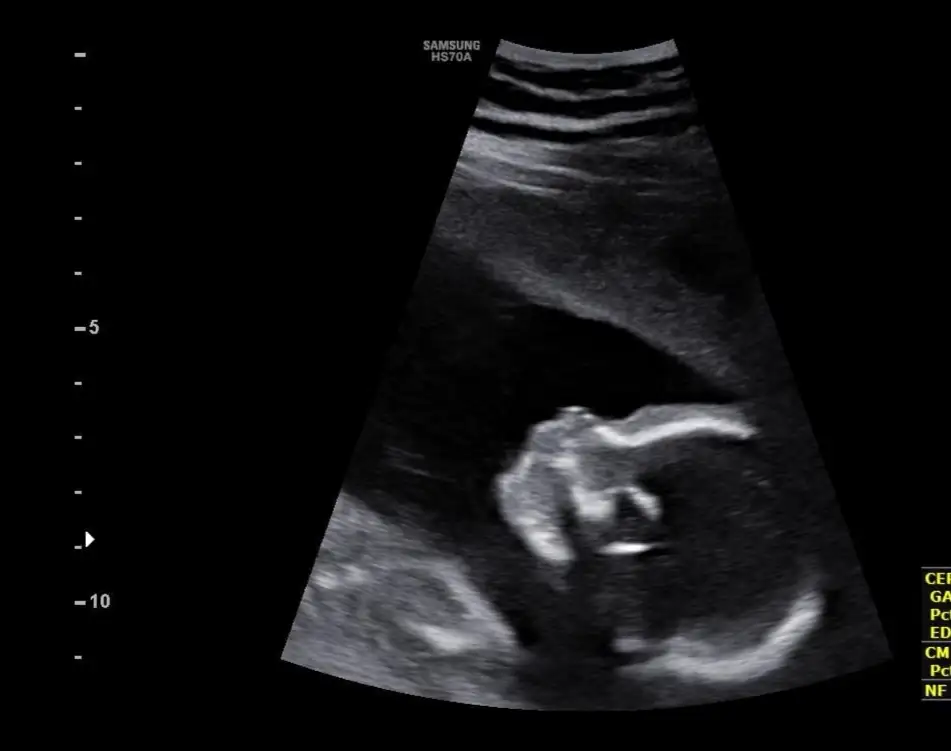

Ay ben hiç dikkat etmedim dur ultrason kağıdıma bakayim sanki yuvarlak benim oğlanın kiBenimki de yuvarlak değil elips gibiaynen bence de böyle iyi. Ben zaten çok severim hafif arkaya bombeli kafaları oğlumun öyle çok şükür. Benim değil mesela olmasını isterdim